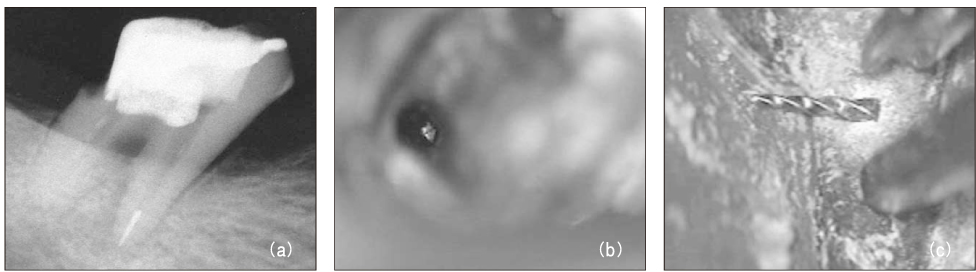

Figure 3

File separation in the root canal (a, b) and remove using ultrasonic device under microscope (c).

Figure 3 File separation in the root canal (a, b) and remove using ultrasonic device under microscope (c).